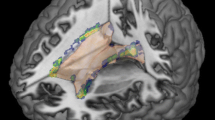

We detected cortical lesions in 32 of 42 patients (76 %). The highest occurrence of cortical lesions was found bilaterally in the parahippocampal gyrus (Fig. 1). Twenty-five percent of the CL patients showed at least one cortical lesion in this region. An overview of the atrophy measurements in the three groups is given in Fig. 2. The three groups differed significantly from one another with regard to BPF (F(2) = 22.4, p < 0.001), TVW (H(2) = 20.9, p < 0.001) and global cortical thickness (F(2) = 11.6, p < 0.001). Bonferroni-corrected post-hoc analyses revealed a reduction of BPF in CL patients relative to HC (p < 0.001) as well as an enlarged TVW (p < 0.001). In contrast, the BPF and TVW values of nCL patients did not differ from those of CL patients or controls. Furthermore, Bonferroni-corrected post-hoc analyses revealed a reduction of global cortical thickness in CL patients compared to HC (p < 0.001) and nCL (p = 0.029) patients, while HC and nCL patients did not differ from one another. Regarding the FLAIR-hyperintense lesion volume, no significant difference (p = 0.064) was observed between the two patient groups.

Spatial distribution of cortex-involving lesions in the CL patient group. Overlap plot based on all normalized cortex-involving lesions found in all CL patients. Lesion frequency across the sample is displayed for every depicted voxel. The bar indicates the number of patients showing damage to a particular voxel. a) Axial and coronal views of lesion frequency. b) and c) Highest lesion overlap was found in the bilateral parahippocampal gyrus (MNI coordinates in b). Image orientation follows the radiological convention (right on left side)

We detected DIR-hyperintense cortical lesions in 76 % of our RRMS patients, supporting the notion of a high prevalence of these lesions [16]. In further agreement with previous findings [41], we observed an uneven spatial distribution of cortical lesions over the cerebral cortex, with a prominent accumulation in memory-relevant mesiotemporal regions, particularly in the bilateral parahippocampal gyrus. While the importance of the hippocampus for memory function is known since the classical description of the patient H.M. in 1957 [42], parahippocampal involvement in memory functions was recognized only two decades ago [43]. Squire and Zola-Morgen identified the anatomical components of what is termed the medial temporal memory system [44]. By now it is well known that bilateral damage to the medial temporal lobe causes severe learning and memory impairments. This relationship has also been shown in MS patients. Learning and memory is the most frequently disrupted cognitive domain in MS, reported in 40–60 % of patients [45]. Moreover, Coebergh et al. [46] described a patient with acute memory impairment, associated with hippocampal and cortical lesions. Cortical lesions were also associated with cognitive decline in a group of 13 MS patients [17]. In this study, a significant correlation between hippocampal lesion load and visuospatial memory was observed. Based on the present and previous findings, we thus conclude that mesiotemporal cortical lesions are highly prevalent in RRMS patients and play a crucial role in the development of mnestic dysfunction.